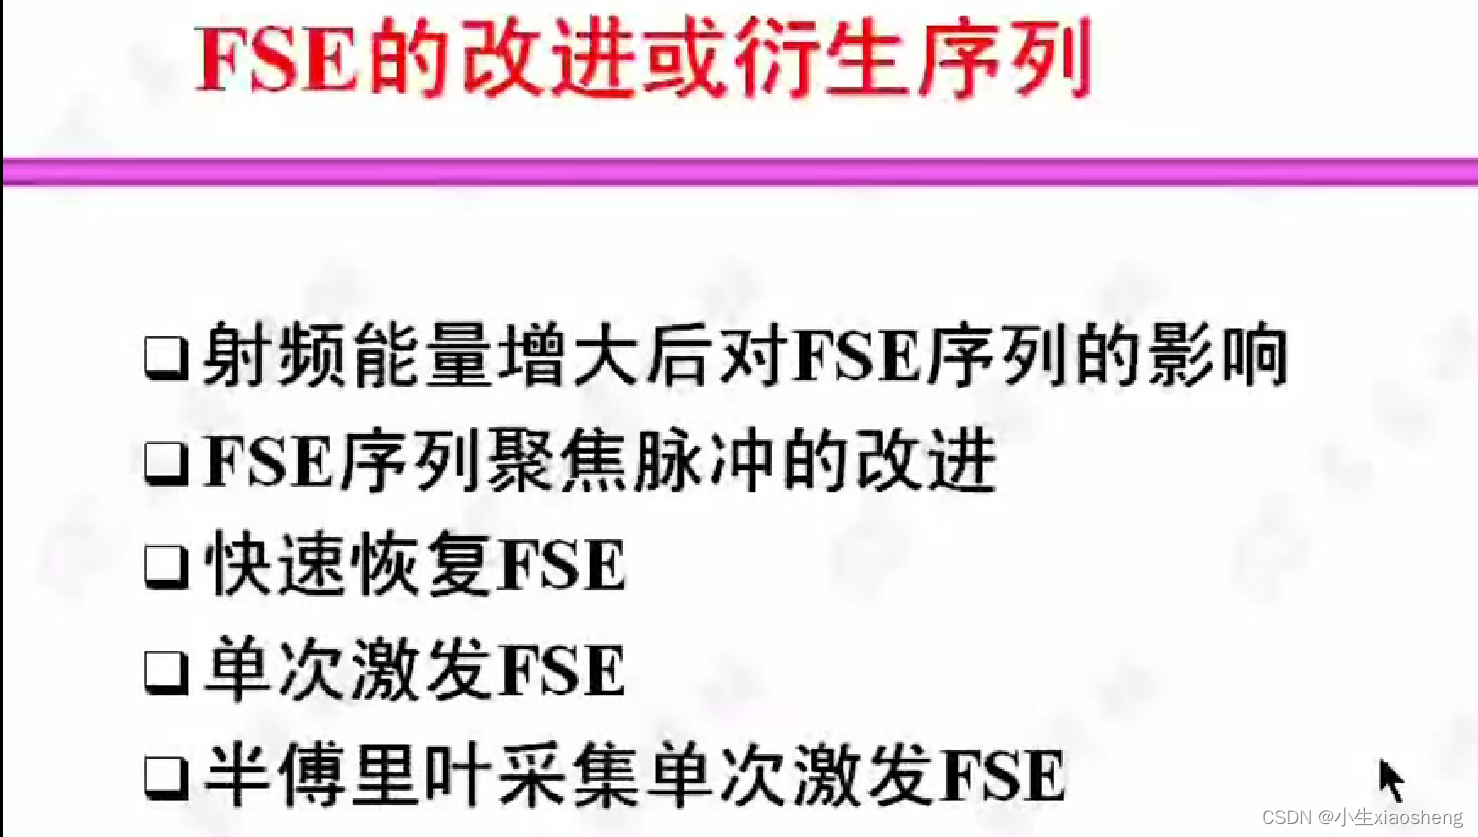

通过对上面几种小改进,那么最后FSE的图片就会得到一定精度的提升。

一一对应:射频能量放大之后ES对应时间就减少了;聚焦就是改变180度角度,慢慢增大到180度,这样图片就变清楚一点;快速恢复就是添加一个负90度脉冲让其更快恢复;单次激发就是90度之后全部为180度把整个K空间填满;半傅里叶采集单次激发FSE=半傅里叶技术+单次激发+FSE原理就是K空间理论上两边是对称的,所以我们就脉冲一半,剩下的就用这一半来填充。